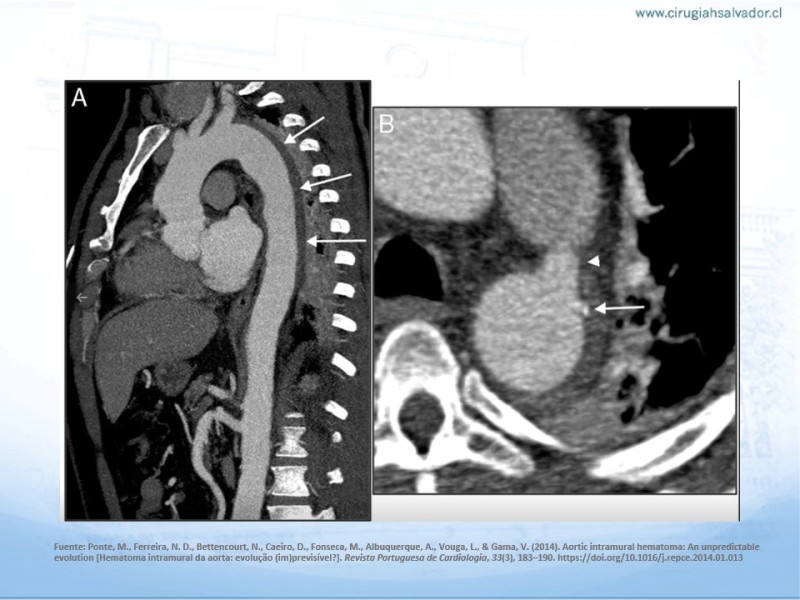

Síndrome aórtico agudo

Cirugía Cardíaca

| Autor: Dr. Nicolás Pimentel P.